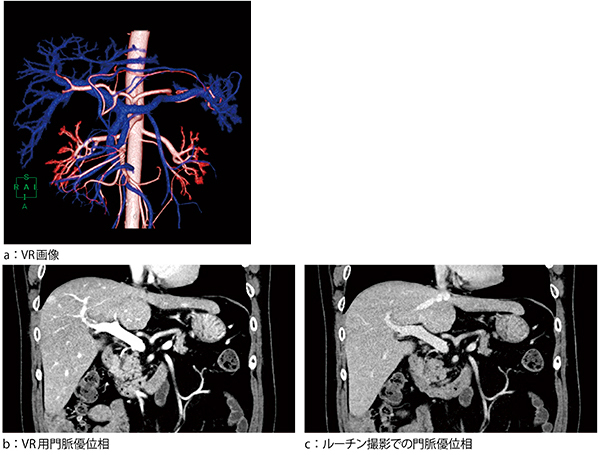

手術支援画像

外科より胃がんの手術の前に動脈と門脈の走行を確認したいとの依頼があり,VR画像を作成した(図1 a)。当院の通常のルーチン撮影では門脈のCT値が低く作成が困難であったため,VR画像の作成に適した造影剤の注入時間と撮影タイミング,撮影条件を考え,見直した。当院のルーチン撮影では,600mgI/kgを30秒注入,腹腔動脈レベルの大動脈でモニタリングし,120HU以上のCT値上昇があったタイミングから18秒delay・35秒delayで後期動脈相・実質相を120kVで撮影していたが,術前の手術支援画像の際は600mgI/kgを25秒注入し,モニタリングは変えず,7秒delay・20秒delayで早期動脈相・門脈優位相を100kVで撮影するようにした(図1 b,c)。シーメンス社の自動管電圧最適化機構“CARE kV”をセミオートで使用し,被ばくの増加を可能なかぎり抑え,体型に依存せずCNRが120kVの撮影より上昇するように設定している。マルチボリュームの機能を使い,早期動脈相と門脈優位相の2相でVR画像を作成した(図2)。

図1 術前の手術支援画像

a:動脈と門脈の走行および位置関係を描出

b,c:ルーチン撮影(c)と比べVR用撮影(b)では,門脈のCT値が上昇しているのが確認できる。

肝臓とのコントラストが明瞭なためVR画像作成が容易になった。